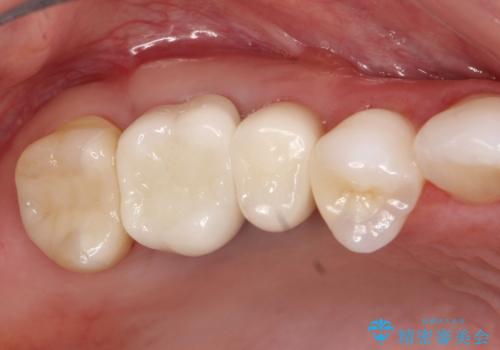

歯周外科・根管治療による長期予後を期待する奥歯の治療

→セラミッククラウンの製作

詰め物の種類:e.max press In

かぶせ物の種類:PFZ Standard